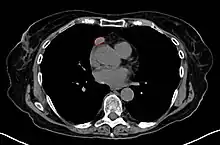

Imaging

A chest X-ray may identify widening of the mediastinum suggestive of thymoma, but computed tomography or magnetic resonance imaging (MRI) are more sensitive ways to identify thymomas and are generally done for this reason.[42] MRI of the cranium and orbits may also be performed to exclude compressive and inflammatory lesions of the cranial nerves and ocular muscles.[43]

As thymomas are seen in 10% of all people with the MG, they are often given a chest X-ray and CT scan to evaluate their need for surgical removal of their thymus glands and any cancerous tissue that may be present.[22][41] Even if surgery is performed to remove a thymoma, it generally does not lead to the remission of MG.[75] Surgery in the case of MG involves the removal of the thymus, although in 2013, no clear benefit was indicated except in the presence of a thymoma.[80] A 2016 randomized, controlled trial, however, found some benefits.[81]